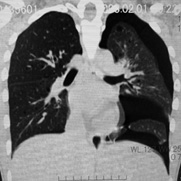

臨床的には進行性肺嚢胞化, くり返す肺気腫, 乳び性胸水貯留が特徴で, 多くの症例では進行性に呼吸不全となる*1

LAM患者さんに認められた両側肺気腫(右図:胸部CT)

firstCT.jpg

secondCT.jpg

初診時CT(左)から2年後のCTでは肺の嚢胞化が著明となっている。